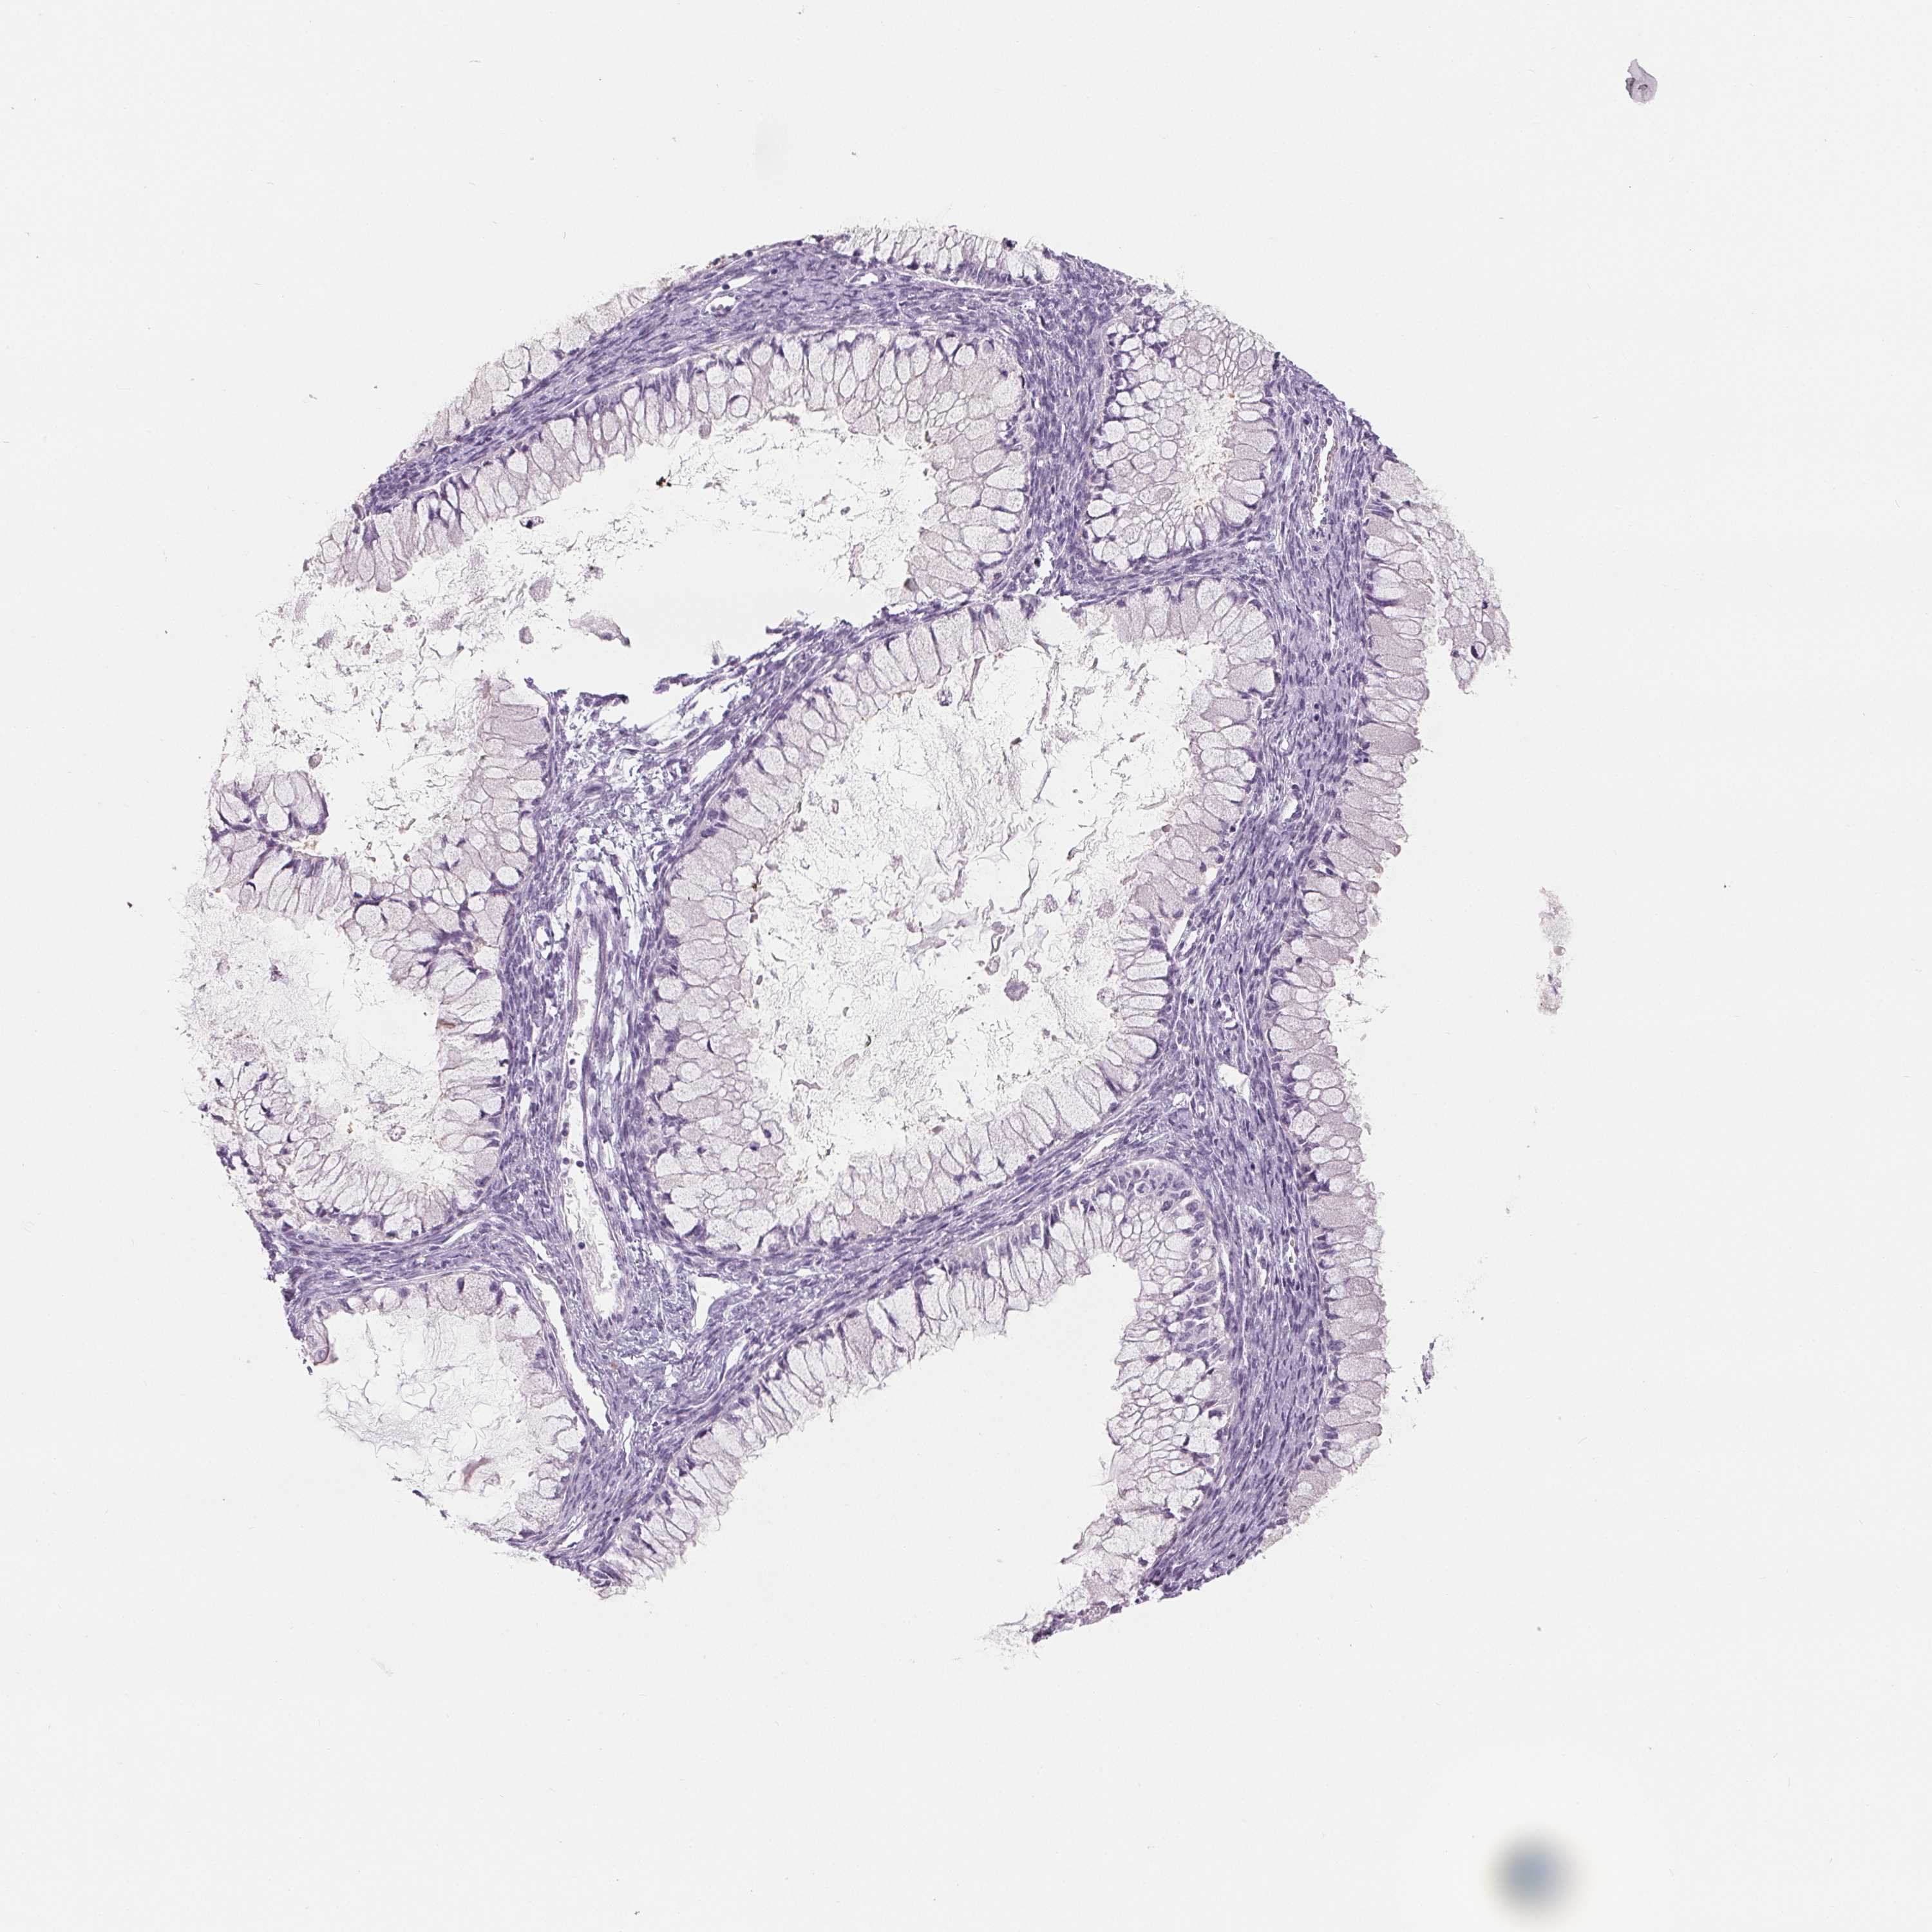

OVARIAN CANCER - Protein expressioni

A mouse-over function shows sample information and annotation data. Click on an image to view it in a full screen mode. Samples can be filtered based on level of antibody staining by selecting one or several of the following categories: high, medium, low and not detected. The assay and annotation is described here.

Note that samples used for immunohistochemistry by the Human Protein Atlas do not correspond to samples in the TCGA dataset.

Antibody stainingi

Antibody staining in the annotated cell types in the current human tissue is reported as not detected, low, medium, or high, based on conventional immunohistochemistry profiling in selected tissues. This score is based on the combination of the staining intensity and fraction of stained cells.

Each image is clickable and will lead to virtual microscopy that enables deeper exploration of all samples and also displays staining intensity scores, fraction scores and subcellular localization as well as patient and tissue information for each sample.

Antibody HPA025070

Antibody HPA025293

Antibody HPA027233

Cystadenocarcinoma, serous, NOS

Cystadenocarcinoma, mucinous, NOS

Carcinoma, endometroid